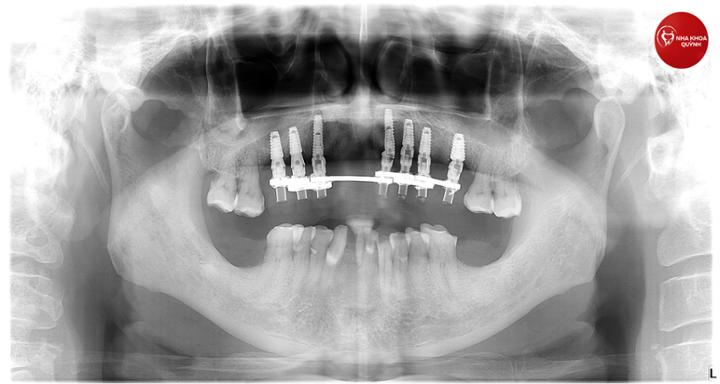

Tùy vào trình trạng sức khỏe răng miệng của từng bệnh nhân, sau khi nha sĩ thăm khám, chụp phim sẽ chẩn đoán và đề nghị phác đồ điều trị phù hợp.

Một răng Implant có cấu tạo gồm 3 phần:

Trụ Implant bằng Titanium, được đặt vào xương hàm ở vị trí mất răng

Mão răng sứ: được thiết kế có hình dáng, màu sắc và chức năng như răng thật, độ bền có thể vượt trội hơn so với răng thật

Khớp nối Abutment: kết nối răng sứ với trụ Titanium.